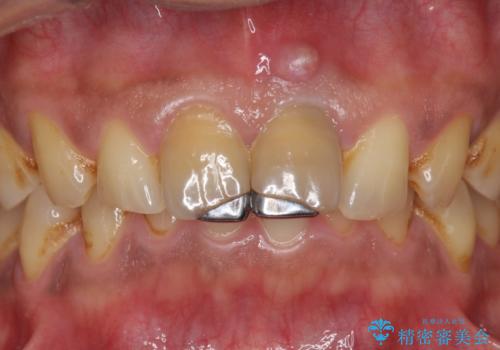

- 体調により前歯部の歯ぐきから出血や膿が出ることの改善を求めて来院されました。

X線写真より、根尖部に透過像が認められ根管治療・ファイバーコア築盛・セラミッククラウンの作製が必要な状態です。

歯ぐきからの出血・排膿について

歯ぐきからの出血・排膿がある場合、根管内の感染や 歯肉炎・歯の破折などが考えられます。